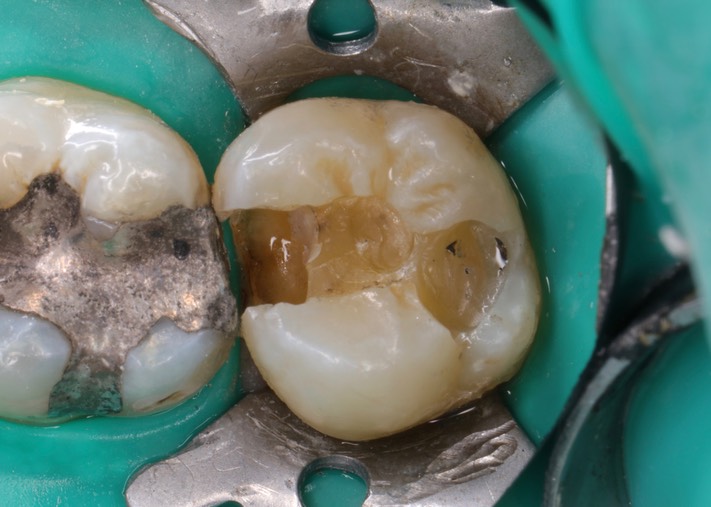

Mendel Sato #2 amalgam removal